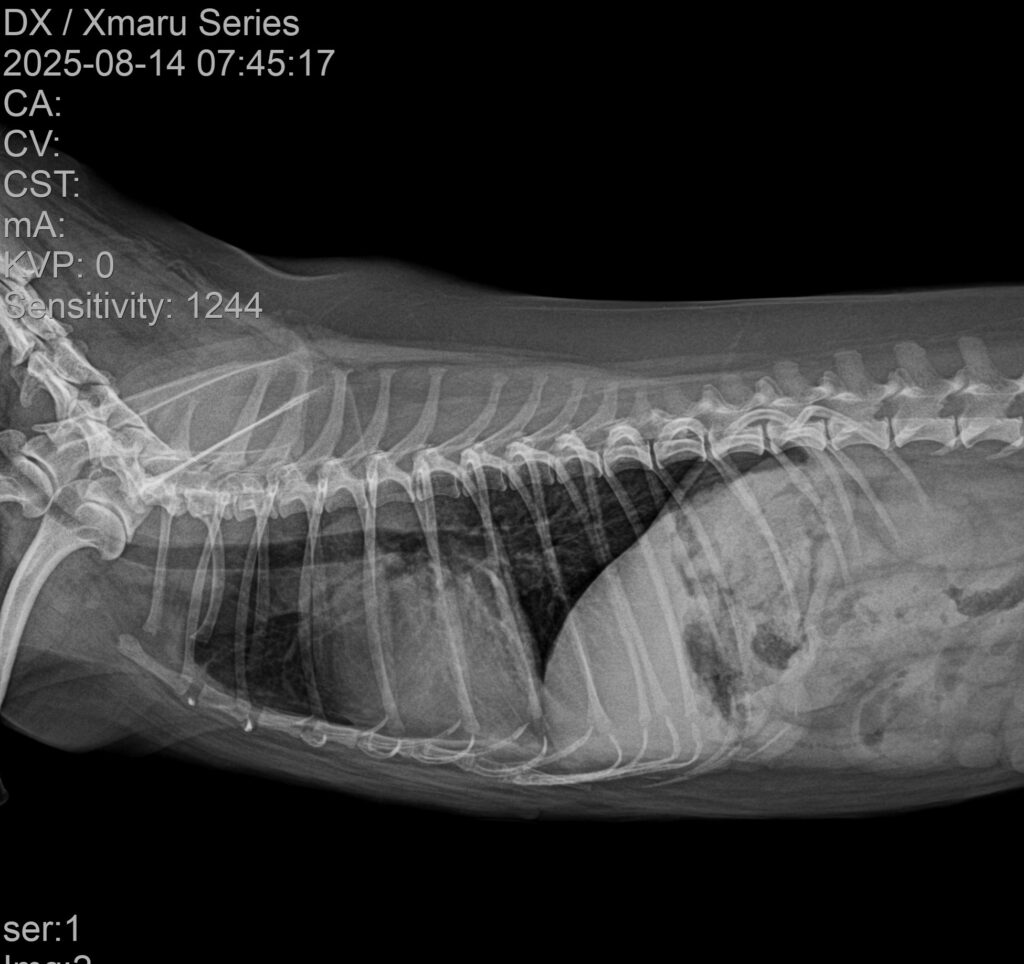

✔ 폐야 침윤 감소

3일차 방사선에서 이미 뚜렷한 호전이 확인되었으며, 7일차 촬영에서는 초기 침윤 부위가 현저하게 줄어든 모습이 관찰되었습니다.

3일차 방사선 사진 / 출처: 강서YD 동물의료센터